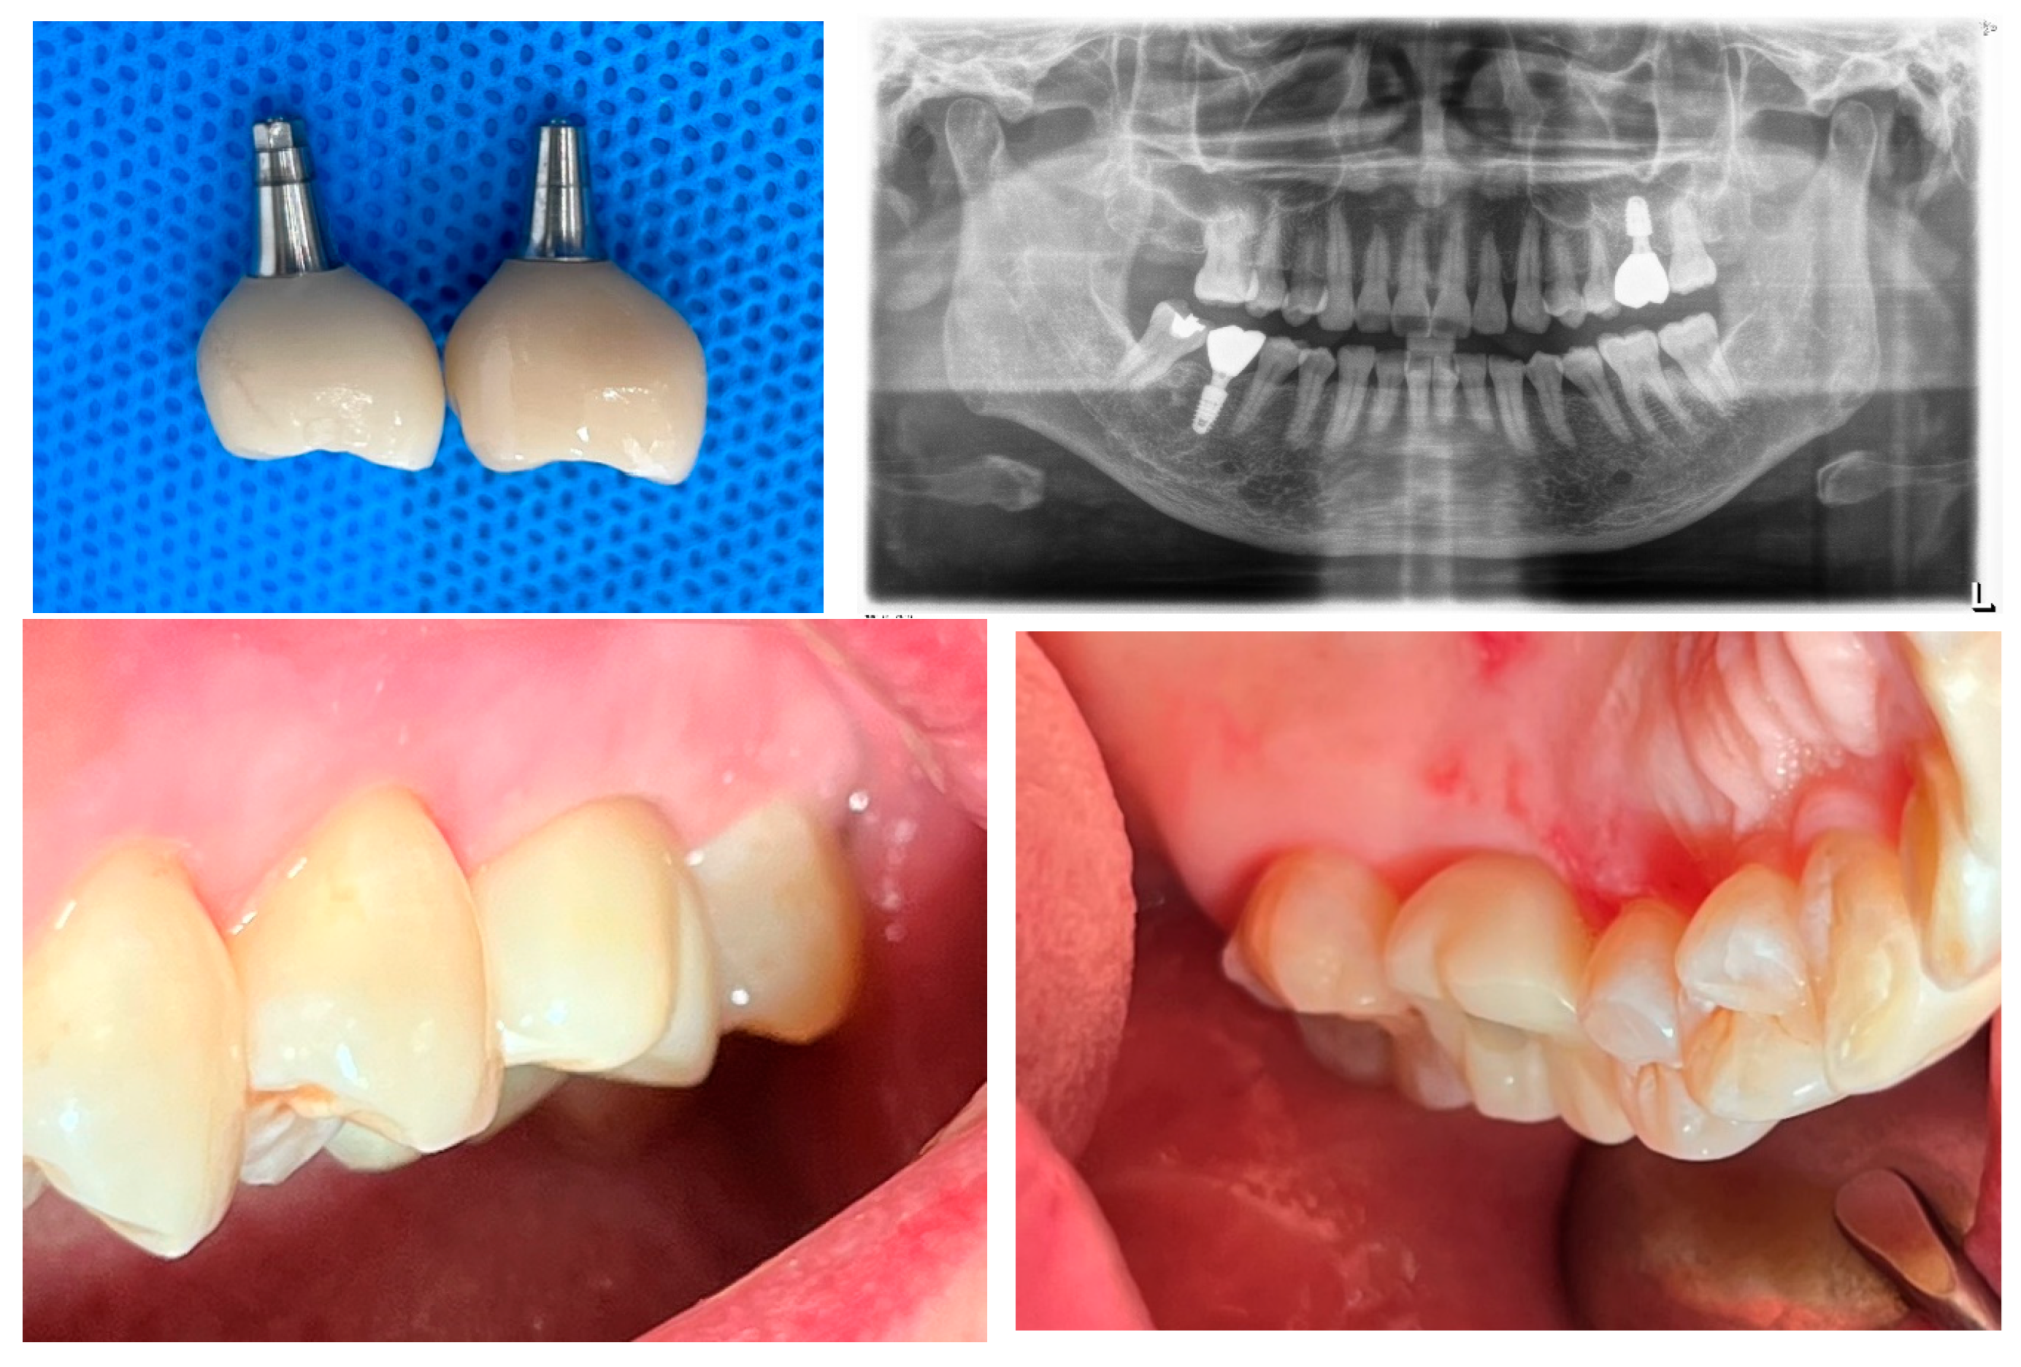

The post-revision evaluation provides significant insights into the structural changes in peri-implant soft tissue and their impact on implant health. Figure 10 compares X-rays from October 2021 and July 2024, illustrating a marked decrease in the Crest to Restoration Distance (CRD) following the restoration modification. (Figure 10) After the reduction achieved by modifying the implant restoration, the gap can now be regarded as entirely filled by peri-implant soft tissue, without voids. From this observation, it can be suggested that maintaining the CRD within a critical range is essential for achieving a stable biological seal, as it ensures the peri-implant soft tissue provides an effective barrier against external irritants and bacterial infiltration.

Figure 10. Comparison of X-rays taken in October 2021 and July 2024 after the restoration revision, demonstrating a decrease in the CRD. When the CRD is maintained within the critical range, it can be inferred that the gap space is occupied exclusively by peri-implant soft tissue, without voids, and the GRD can be represented as Soft Tissue Thickness (STT).

Preprints 151394 g010